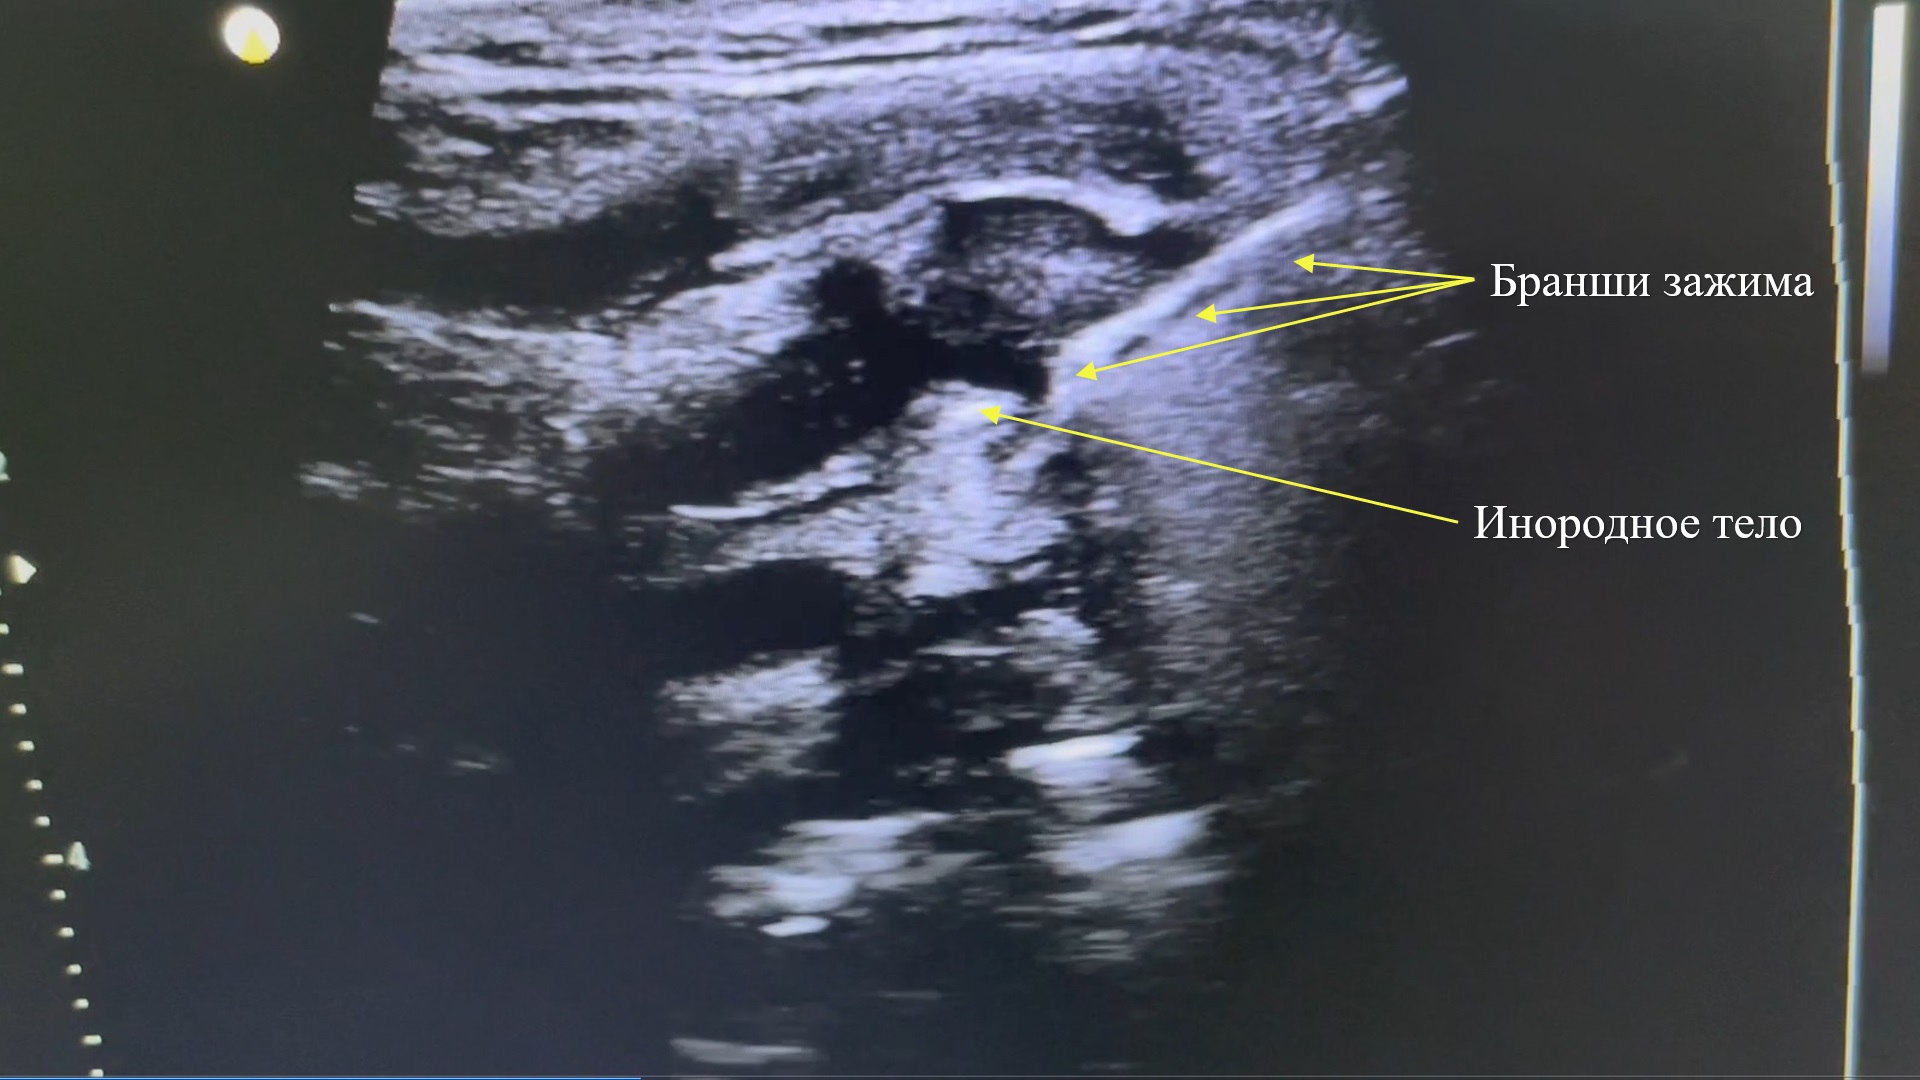

Рис. 5. Бранши зажима с инородным телом.

Fig. 5. Clamp branches with a foreign body.

Оперативное вмешательство (02.12.23 г.) проводилось с использованием местной анестезии раствором новокаина (0,5% - 20,0 мл), под постоянным контролем ультразвуковой диагностической системы «РуСкан 70 П» и линейного датчика L12-3E в дуплексном режиме, методом «свободной руки». Вначале, при помощи шприца (20,0 мл), обходя жизненно важные магистральные сосуды, кончиком иглы выполнен контакт с интересующим нас объектом, для точного определения наличия ИТ. После подтверждения того, что кончик иглы контактирует с металлическим ИТ, выполнено введение раствора новокаина в мягкие ткани вокруг ИТ, для более безопасного и беспрепятственного его удаления, а также отхождения от рядом расположенных мягких тканей и сосудов. Через входное отверстие в рану введен прямой зажим. Под постоянным ультразвуковым контролем зажим низведен до ИТ, выполнен контакт с ним, после чего бранши зажима заведены ниже ИТ и разведены. Путем давящей тракции через кожу линейным датчиком последнее опускалось в раскрытые бранши зажима, после чего бранши зажима закрывались, инородное тело фиксировалось и медленными круговыми движениями эвакуировалось из раны. Также при помощи ультразвукового контроля выполнена санация раны с последующим дренированием резиновым перчаточным выпускником, длиной около 7 см, до места изначального нахождения инородного тела, при контрольном УЗИ признаков кровотечения из магистральных сосудов не выявлено. Швы на кожу не накладывались с целью профилактики развития инфекционных раневых осложнений, так как рана была размером до 4 мм. Наложена асептическая повязка.